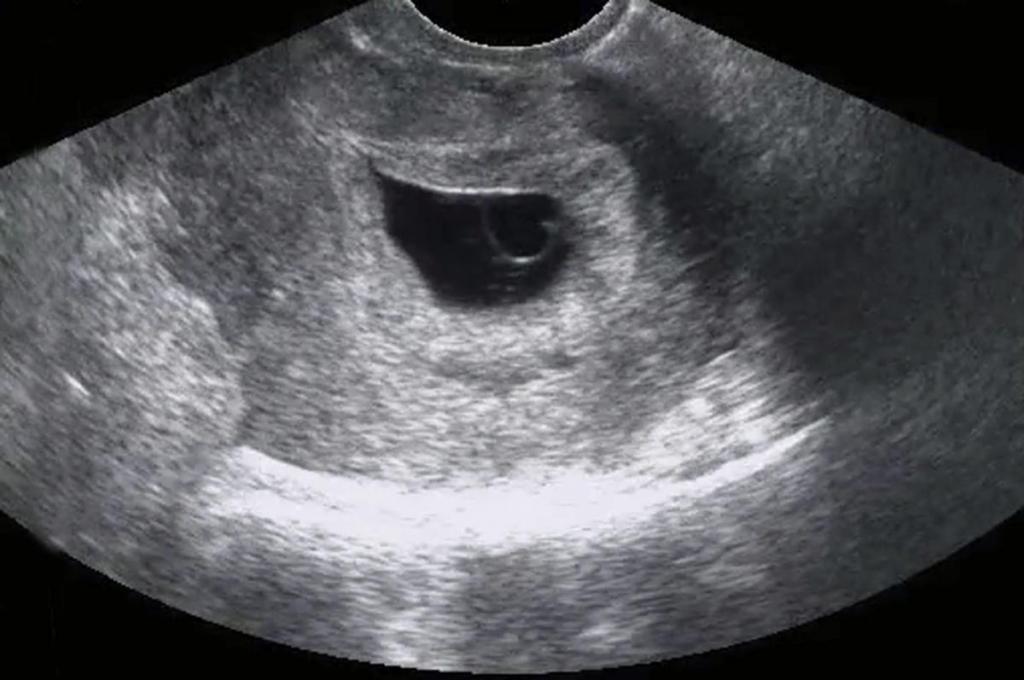

Калифорнийские исследователи разработали чип, с помощью которого научились определять скопление трофобластов в крови — признак патологии плаценты у женщин с рубцом матки. Это позволит выявлять врастание плаценты в стенки матки даже на ранних стадиях.